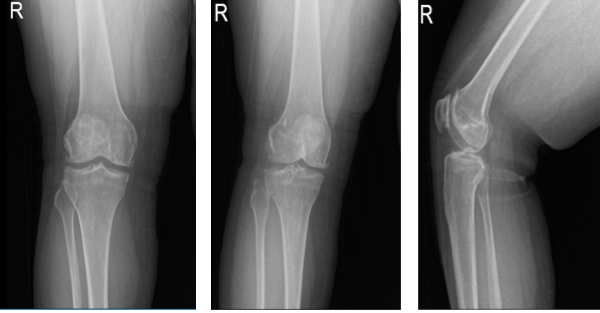

X-rays were done, the distal femur, patella, proximal tibia and proximal fibula demonstrate intact cortical margins with no acute fracture. The medial, lateral and patellofemoral joint spaces are well-maintained. There is mild medial osteophyte formation. There is mild patellofemoral osteophyte formation.

There is no radiographic evidence of a joint effusion. There is no radiographic evidence of soft tissue swelling. The impression is there are mild osteoarthritic degenerative changes. There are no acute fractures.

Which showed lateral tilt of the patella towards the trochlea along with advanced patellofemoral arthritis with mild medial compartment arthritis. Also, the MRI was done to confirm the findings.

Right knee X-ray AP Lateral and Oblique 3 views